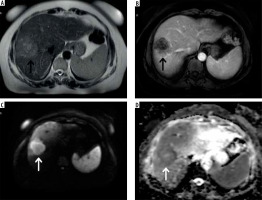

The standard MRI protocol identified 197 liver lesions (175 metastatic, 18 benign, 4 indeterminate). Among these, 142 lesions (72.1%) were larger than 10 mm, with the majority being metastatic (140/142). Of the 55 lesions ≤ 10 mm, most were metastatic (35/55). In Figure 1, the Standard MRI protocol is exemplified for metastasis characterization.

59-year-old male with metastatic colorectal cancer. A) Axial T2W sequence shows a hyperintense lesion in the liver right lobe anterior segment (black arrow). B) Axial T1W contrast-enhanced image shows hypointense lesion with peripheral contrast enhancement (black arrow). C) Axial DWI (b = 800). D) ADC map image shows diffusion restriction (white arrow), both readers characterised this lesion as malignant